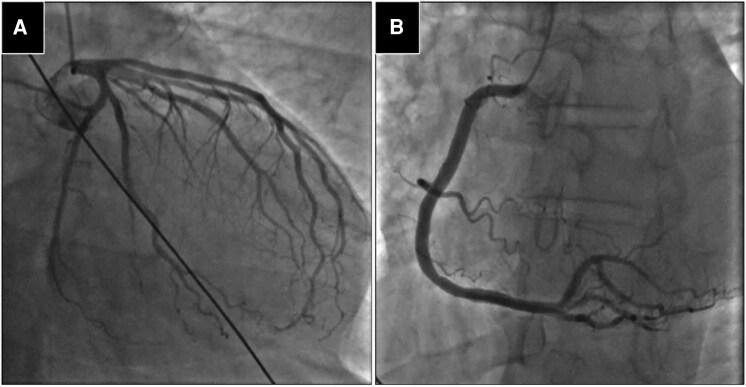

A 37-year-old man with a history of panic disorder was transported to our institute after he experienced hyperventilation during a panic attack and developed chest pain and a subsequent loss of consciousness. During transportation, ventricular fibrillation was observed on electrocardiography, and sinus rhythm was successfully restored with defibrillation. Suspecting hyperventilation-induced coronary vasospasm, a hyperventilation test was performed, which induced 90% coronary spasm accompanied by chest pain. An acetylcholine (ACh) provocation test revealed total occlusion of the left main bifurcation, with significant ischaemic ST-T elevation. Medication with a calcium channel blocker (nifedipine 40 mg per day), nitrate (isosorbide dinitrate 40 mg per day), and statin (rosuvastatin 20 mg per day) was initiated. Three months later, a repeat ACh provocation test performed to assess response to the medications revealed 90% stenosis with ischaemic ST-T changes and chest discomfort. Subsequently, a subcutaneous cardioverter defibrillator was implanted to address refractory vasospastic angina.

一名有惊恐障碍病史的37岁男性在惊恐发作期间经历过度通气并出现胸痛,随后失去意识,被送往我院。在转运过程中,心电图显示心室颤动,通过除颤成功恢复窦性心律。怀疑是过度通气诱发的冠状动脉痉挛,进行了过度通气试验,该试验诱发了90%的冠状动脉痉挛并伴有胸痛。乙酰胆碱(ACh)激发试验显示左主分叉完全闭塞,伴有明显的缺血性ST-T段抬高。开始使用钙通道阻滞剂(硝苯地平每日40毫克)、硝酸盐(硝酸异山梨酯每日40毫克)和他汀类药物(瑞舒伐他汀每日20毫克)治疗。三个月后,为评估药物反应而进行的重复ACh激发试验显示有90%的狭窄,伴有缺血性ST-T改变和胸部不适。随后,植入了皮下心脏复律除颤器以治疗难治性血管痉挛性心绞痛。